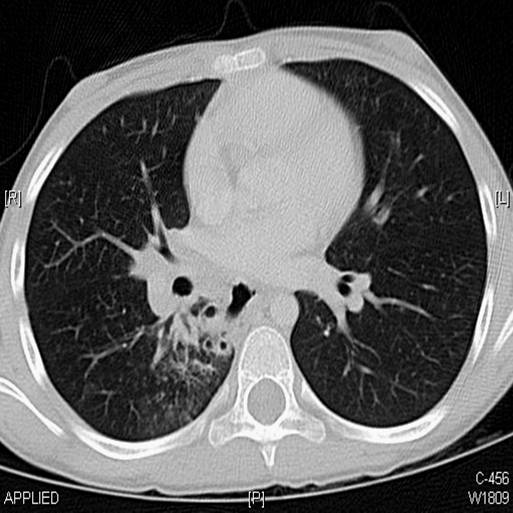

A CT scan of chest was done.

The following screen shows the images from the Chest CT.

| Figure 4-a | Figure 4-b | Figure 4-c |

| Figure 4-d | Figure 4-e | Figure 4-f |

| Figure 4-g |

||